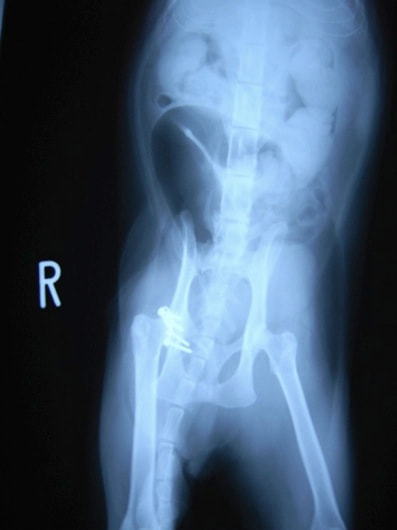

骨盤骨折 : 症例1 | 症例2 | 症例3 | 症例4